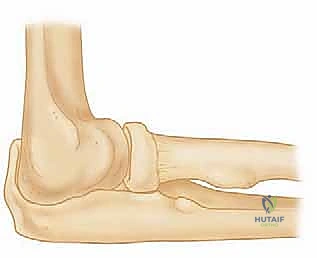

لكي ندرك تماماً حجم المشكلة وكيفية علاجها، يجب علينا الغوص في التشريح المعقد لمفصل الكوع. يتكون هذا المفصل من التقاء ثلاث عظام رئيسية:

1. عظم العضد (Humerus): عظمة الذراع العلوية.

2. عظم الزند (Ulna): العظمة الداخلية للساعد (جهة الإصبع الصغير).

3. عظم الكعبرة (Radius): العظمة الخارجية للساعد (جهة الإبهام).

تتصل هذه العظام معاً لتشكل ثلاثة مفاصل فرعية داخل كبسولة مفصلية واحدة. للحفاظ على هذه العظام في مكانها وتوفير الاستقرار الديناميكي أثناء الحركة، توجد شبكة معقدة من الأربطة. في الجهة الخارجية (الوحشية) من الكوع، يوجد ما يُعرف بـ مركب الرباط الجانبي الوحشي (LCL complex).

هذا المركب ليس مجرد خيط واحد، بل هو بنية تشريحية ثلاثية الأبعاد تتألف من أربعة مكونات رئيسية مترابطة:

- الرباط الزندي الجانبي الوحشي (Lateral Ulnar Collateral Ligament - LUCL): يُعرف أيضاً في بعض المراجع الطبية بالرباط الكعبري الزندي العضدي (RUHL). هذا الرباط هو "نجم العرض" والهدف الأساسي في أي عملية إعادة بناء. إنه المثبت الأقوى والأكثر أهمية ضد عدم الاستقرار الدوراني الخلفي الوحشي (PLRI). ينشأ هذا الرباط من نقطة محددة جداً على اللقمة الوحشية لعظم العضد (Lateral Epicondyle) ويمتد ليلتف حول رأس الكعبرة ويتصل بعمق وقوة في عرف العضلة الكابة للزند (Supinator Crest of the Ulna).